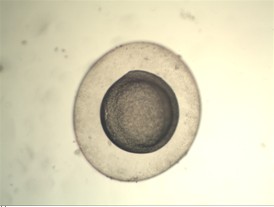

下面是實(shí)拍的一些圖片:

體視顯微圖片

體視顯微圖像